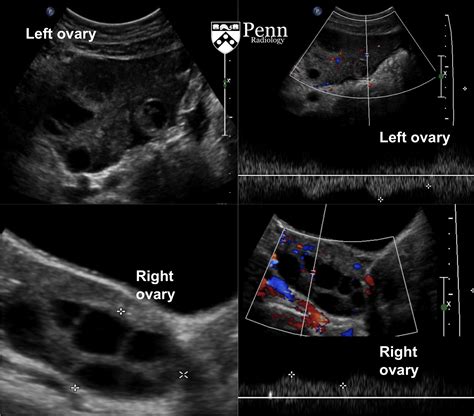

Enlargement of the Ovary

The most common finding is an increase in the size of the affected ovary. This occurs because the obstruction of the venous outflow—the veins responsible for carrying blood away from the ovary—leads to congestion, swelling, and edema. Often, the ovary will appear significantly larger than the unaffected contralateral ovary.

Abnormal Blood Flow Patterns

While the absence of flow is the most definitive sign, it is also a late finding. Radiologists look for subtle changes, such as high-resistance flow in the ovarian artery, which suggests the ovary is struggling to receive blood against the pressure of the twist. The presence of a “whirlpool sign”—a twisting of the vascular pedicle—is highly specific for torsion, though it can be technically difficult to visualize.